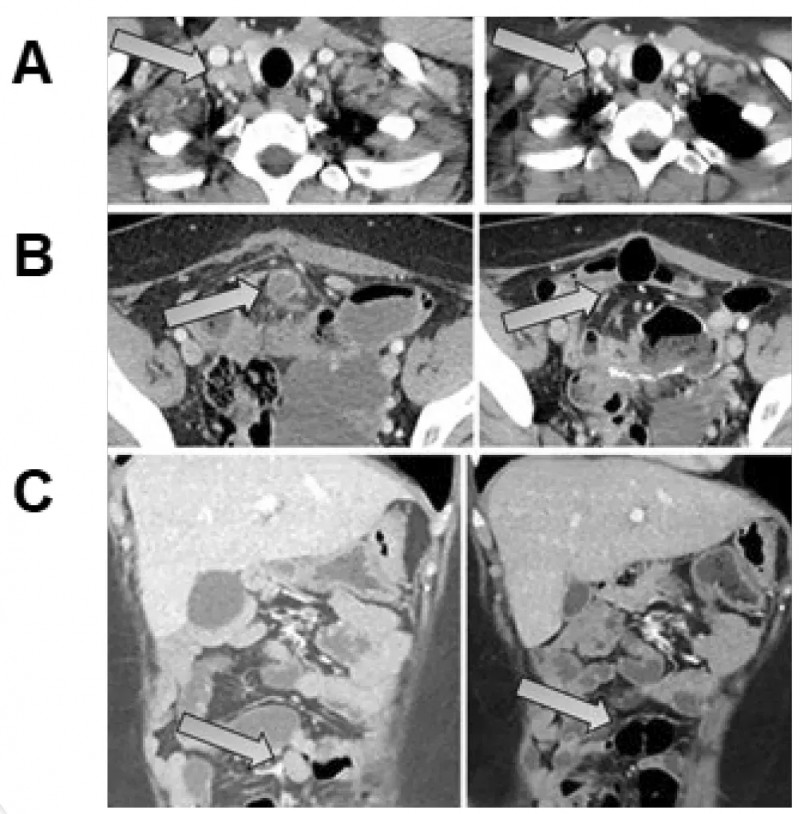

2025年美国癌症研究协会(AACR)年会上,一款创新CRISPR-TIL疗法的首次人体I期临床试验(NCT04426669)公布了震撼数据:一名对传统免疫疗法难治的年轻微卫星不稳定性高(MSI-H)转移性结直肠癌(mCRC)患者,接受治疗后实现临床完全缓解——影像学检查已无法检测到肿瘤病灶,且缓解持续时间超过24个月。

该患者此前对化疗及抗PD-1/CTLA-4联合治疗均耐药,此次疗效不仅为晚期结直肠癌患者点燃了“肿瘤清零”的希望,更标志着TIL细胞疗法在结直肠癌治疗领域迈出了里程碑式的关键一步,为晚期癌症治疗提供了极具价值的临床参考。

▲图源“AACR”,版权归原作者所有,如无意中侵犯了知识产权,请联系我们删除